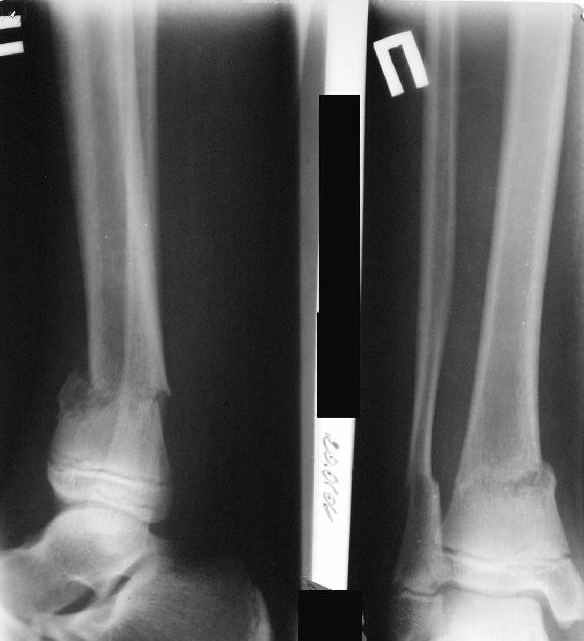

Так как речь зашла непосредственно о травме, см этапные

снимки. Как все было

Первичные

|